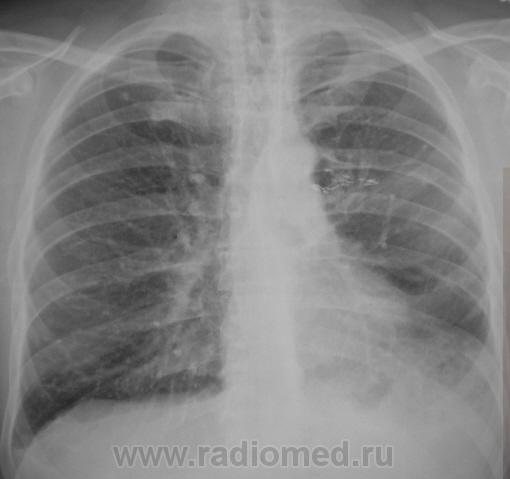

На обзорной рентгенографии ОГК определяется единичный очаг в первом межреберье справа, и множественные очаги в пятом межреберье справа! Правый реберно-диафрагмальный угол спаян! Ателектаз левого легкого? В корне левого легкого определяется тень неправильной формы! Центральный рак? Метастазы? Туберкулез?

А левая верхушка? На томограммах тоже видны изменения.А в корне левого легкого это швы?( почему-то снимки не увеличиваются).Левый корень плотный.Не исключено наличие ателектаза в язычковых сегментах ( или инфильтрации).Боковые будут?Хотелось бы.

Оперирован. Левостороняя лобъектомия по поводу больших размеров туберкуломы. Архива у нас нет, он в "областной конторе".

Думаю, рецидив ТБС. Оперированное левое легкое.

Рецидив справа?

С обеих сторон.

Золотые слова. Коллега фтизиатр, увидев, эти новые снимки очень расстроился и сказал непотребное слово на букву "б", очень расстроился, рецидив, как "пить дать"...

Да, скорей всего получается рецидив. И всё же архив посмотреть надо.